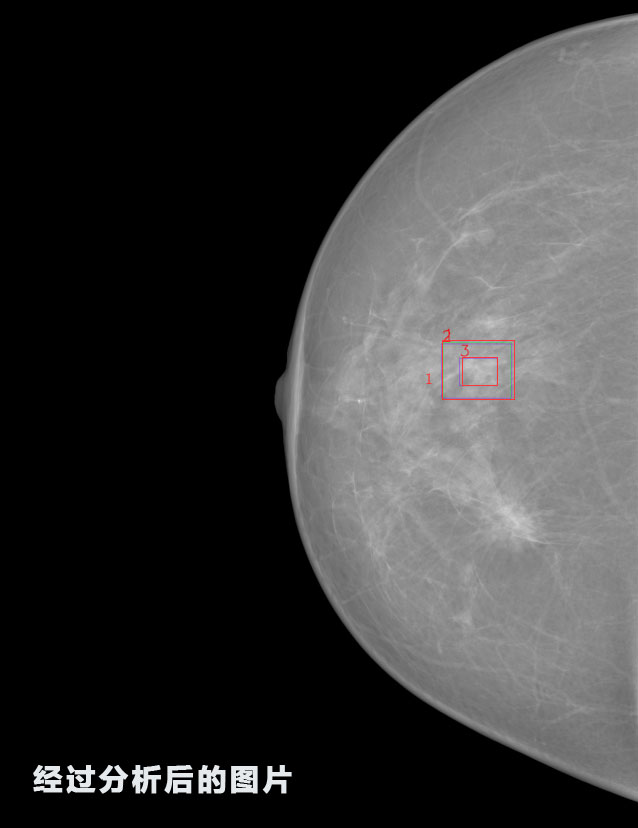

英特健康AI深度學習醫療圖像識別系統案例_乳腺

識別報告:

1.發現良性鈣化,可能性為19.88%---位置框指數:[1796.0867 1359.8237 2058.1372 1582.5334]

2.發現惡意鈣化的可能性為15.18%---位置框指數:[1789.4733 1365.9951 2063.7698 1576.0613]

3.發現惡意鈣化的可能性為12.45%---位于框指數:[1859.3987 1422.3184 2006.5494 1528.2698]